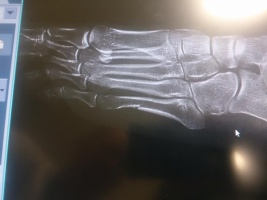

Diagnoza: wielowarstwowe złamanie w lewej stopie. Justyna Kowalczyk komentuje: walczę dalej!

Po sobotnim biegu ukazały się jednak niepochlebne komentarze w stosunku do biegaczki. Justyna Kowalczyk postanowiła wtedy wykonać zdjęcie rentgenowskie. Wykazało złamanie wielowarstwowe w śródstopiu.

– Do zrobienia zdjęcia rentgenowskiego zmusiły mnie opinie „ekspertów”, którzy skomentowali mój występ – mówiła. – Nawet prezes mojego związku powiedział mi, że biegłam ociężale. Zrobiłam zdjęcie, żeby zamknąć im usta. Komentarze, z jakimi się zetknęłam były obraźliwe. A mnie się wydaje, że zasługuję na szacunek jako sportowiec z dużym dorobkiem i jako kobieta.

To, że noga jest złamana przypuszczałam już wcześniej – kontynuowała Justyna Kowalczyk. – Ból był zbyt silny. Gdyby to było zwykłe stłuczenie, już by przeszło. Tymczasem dolegliwość doskwiera mi od trzech tygodni. To nic nie zmienia w planach moich startów. Mam zamiar walczyć. Sprawdziłam, czy mogę biegiem w Toblach, który utwierdził mnie w przekonaniu, że mam po co jechać do Soczi. Tu na miejscu opiekuje się mną dr Szymanik. Ale i tak to ja podejmuję decyzję, bo to moja noga i mój problem. Wystartuję i będę walczyć. I mam to gdzieś, jak to ocenią „eksperci” – zkończyła mistrzyni olimpijska z Vancouver.